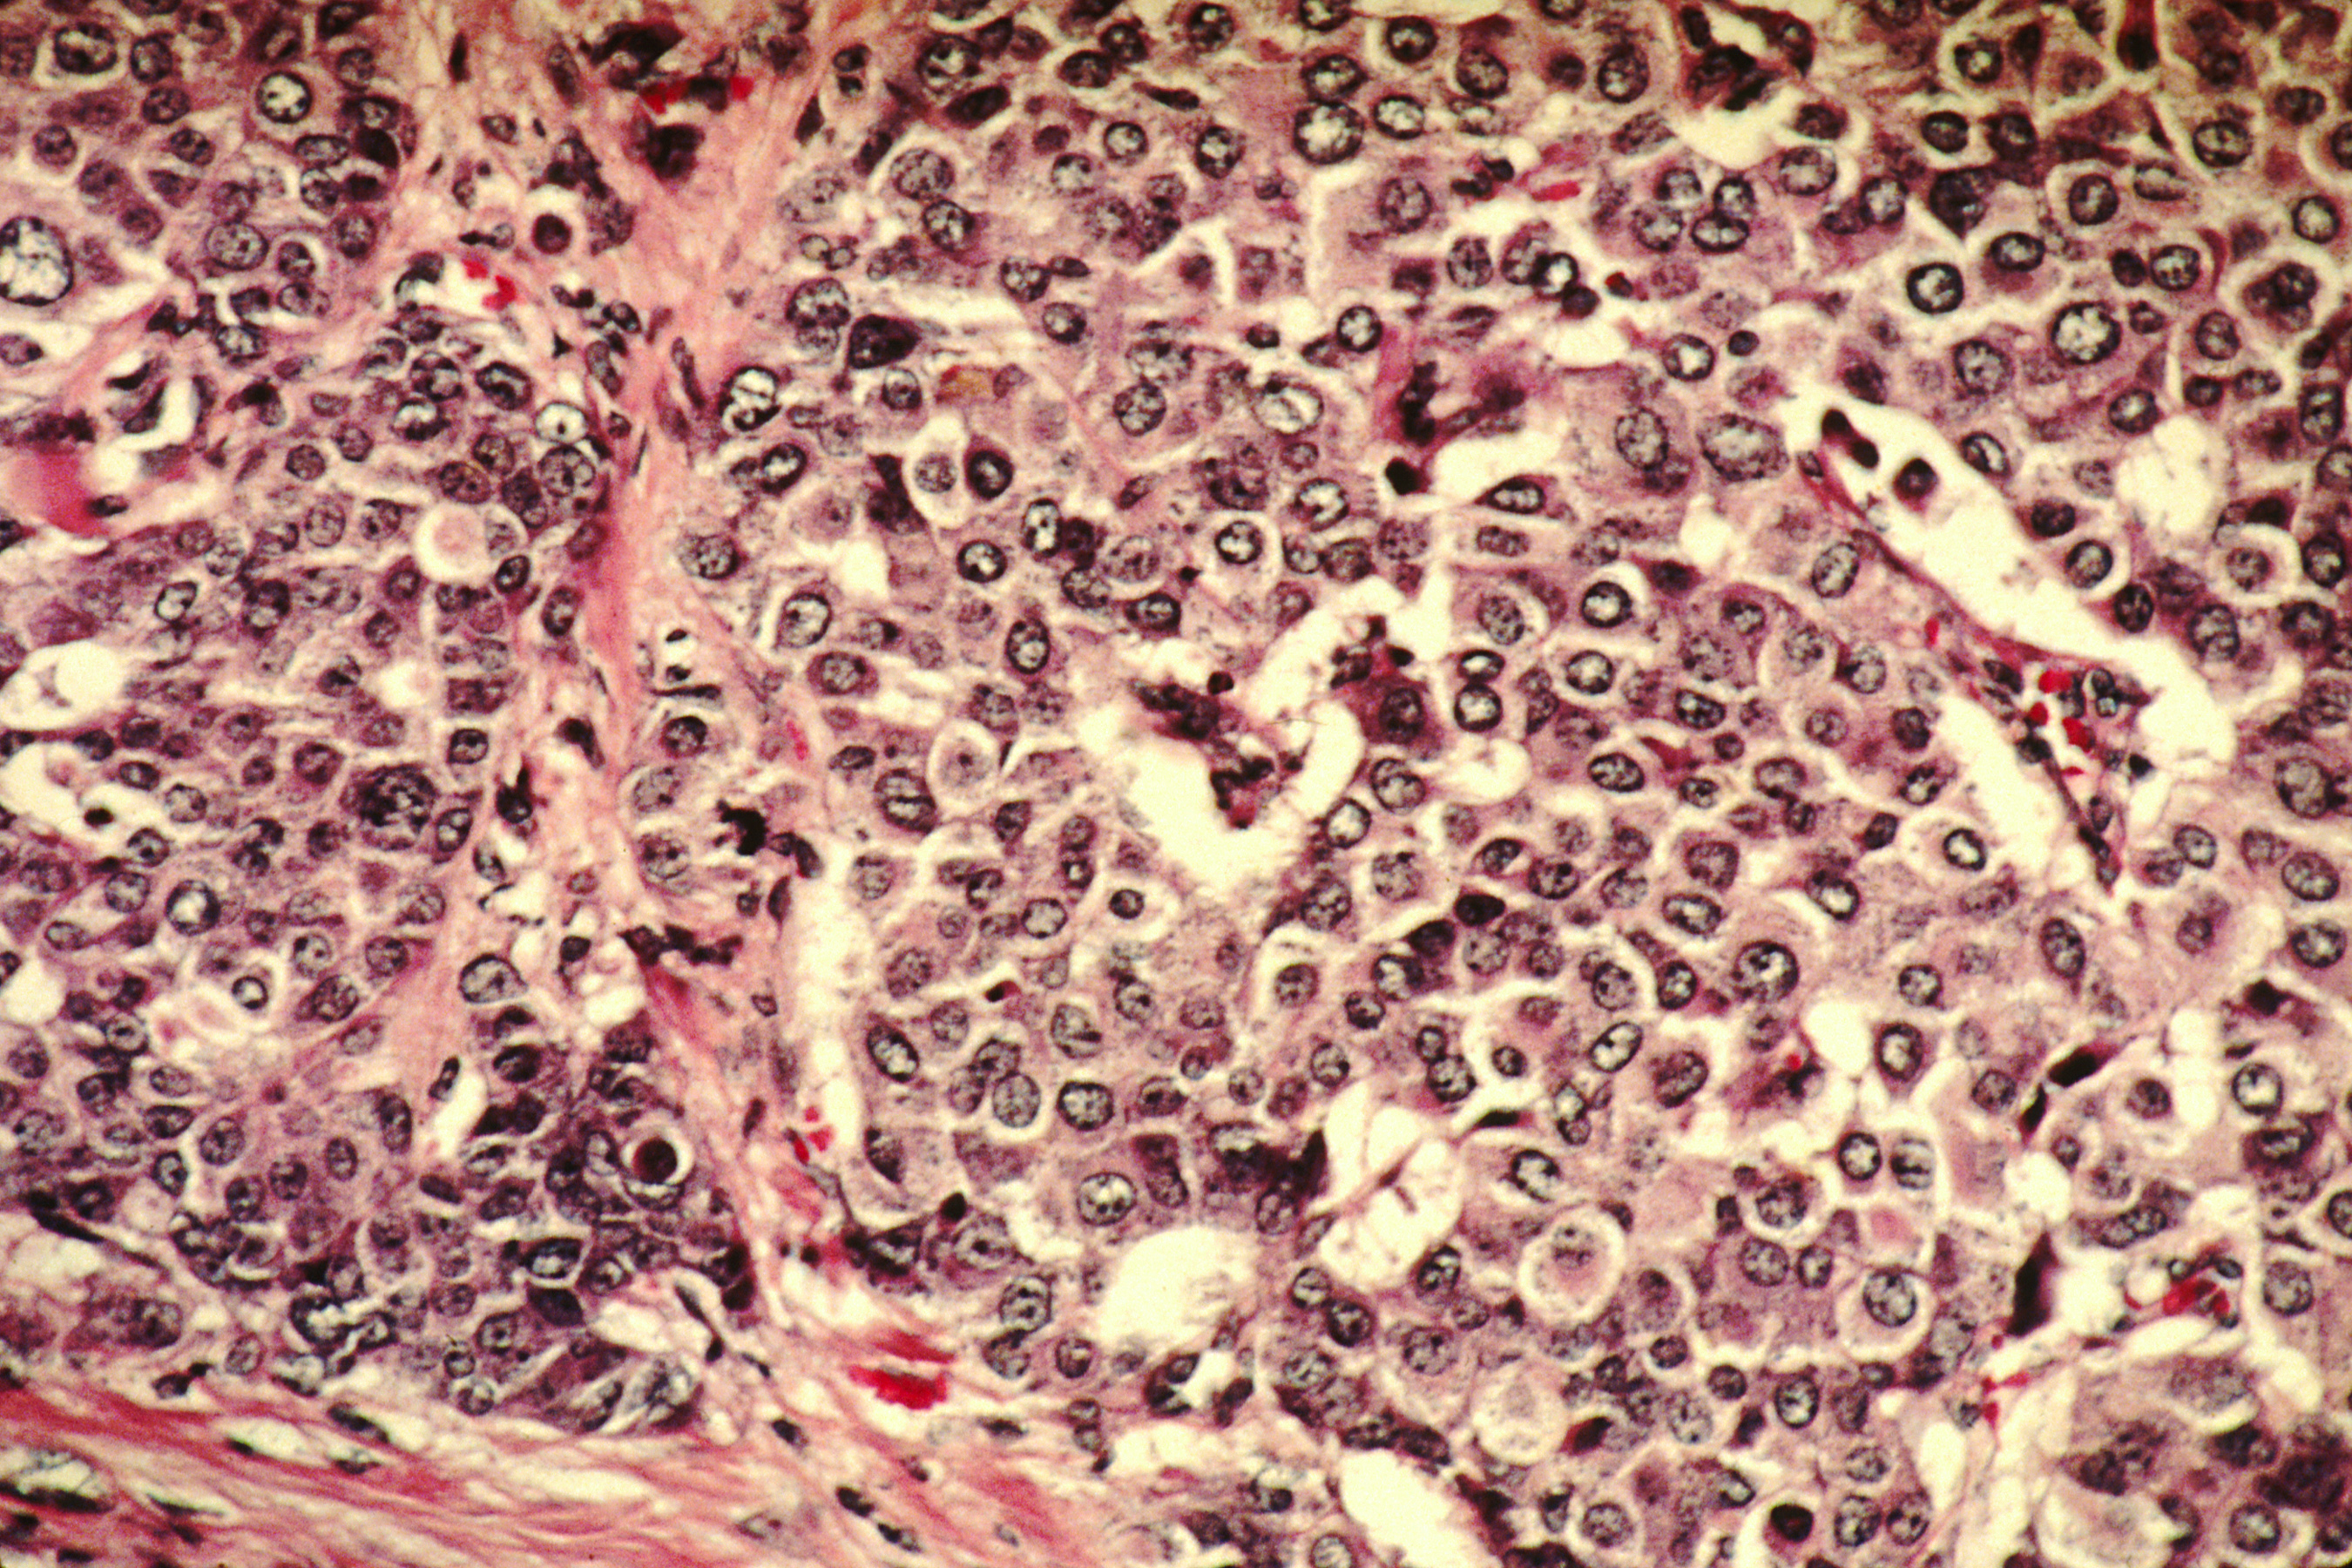

Autofagia y cáncer

La autofagia es un proceso metabólico crucial tanto en condiciones fisiológicas como patológicas. De hecho, en diversas enfermedades se han detectado deficiencias en dicho proceso. El cáncer es una de ellas. Las investigaciones realizadas sobre esta enfermedad han desencadenado una gran cantidad de conocimientos, no sólo de la enfermedad como tal, sino también de los mecanismos biológicos que la acompañan y favorecen su existencia.

Uno de estos es, precisamente, la autofagia. Si la célula detecta que existe algo que no funciona de forma correcta se autodestruye antes de seguir haciendo daño al organismo. Sin embargo, la cura del cáncer todavía es complicada, lo que indica que no todo está tan claro. Tal y como se expone en el artículo al que nos referimos, existen evidencias que demuestran que este mecanismo biológico tiene una doble cara.

Por un lado, desempeña un papel totalmente beneficioso para nuestra salud como protector frente a enfermedades. Para ello, actúa como un servicio de limpieza, contrarresta la inestabilidad del genoma y exceso de factores de crecimiento, así como, captura orgánulos dañados e induce a la iniciación de la muerte celular. Sin embargo, existe la otra cara y es que la autofagia también puede contribuir a la supervivencia del tumor, protegiendo a las células tumorales ante condiciones adversas.

Las células cancerígenas tienen una serie de necesidades que son deficientes en el microambiente en el que se reproducen. Esto cambia cuando hay problemas de salud incrementándose, así, las posibilidades de crecimiento de tales células. Ello es debido a que, a nivel tumoral, el proceso de autofagia aporta nutrientes a las células cancerígenas y regula el proceso inflamatorio inducido por necrosis.